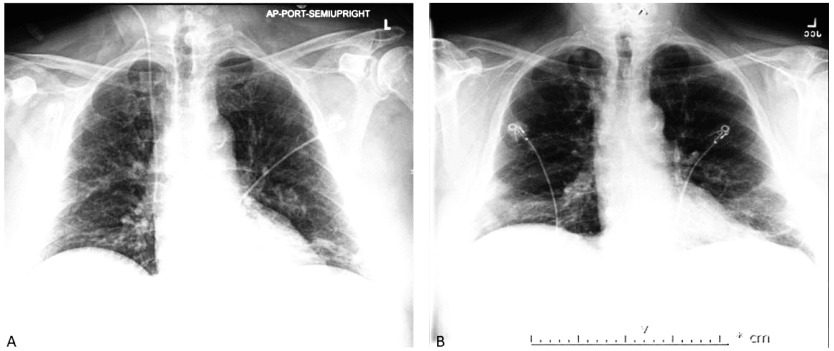

达托霉素是一种环脂肽抗生素,适用于治疗革兰氏阳性菌引起的复杂皮肤感染和菌血症。急性嗜酸性粒细胞肺炎(AEP)是达托霉素的一种罕见但严重的不良反应,由肺组织中的嗜酸性粒细胞聚集引起,可导致呼吸衰竭。早期诊断和治疗对避免严重并发症(包括死亡)至关重要。在此,我们报告了一例老年男性患者的病例,他在开始使用达托霉素治疗 MRSA 菌血症的两周内出现了 AEP 的症状和体征。停用达托霉素并开始为期 5 天的类固醇治疗后,患者的临床症状明显好转,嗜酸性粒细胞也有所下降。急性嗜酸性粒细胞肺炎是达托霉素可能产生的不良反应,尽管这种情况很少见,但仍应引起注意。可以通过典型症状、嗜酸性粒细胞增多和胸部X光片显示肺部浸润来进行早期识别。迅速停用达托霉素,并辅以类固醇治疗和支持性护理,通常可使患者的临床症状明显缓解。

Daptomycin is a cyclic lipopeptide antibiotic that is indicated for the treatment of complicated skin infections and bacteremia caused by gram positive organisms. Acute eosinophilic pneumonia (AEP) is a rare, but serious adverse effect of daptomycin and caused by accumulation of eosinophils in the lung tissues, and can lead to respiratory failure. Early diagnosis and management of this condition is crucial to avoid severe complications, including death. Herein, we report a case of an elderly man who presented with signs and symptoms of AEP within two weeks of initiation of daptomycin for the treatment of MRSA bacteremia. The patient showed significant clinical improvement and decline in eosinophils upon discontinuation of daptomycin and starting a 5-day steroid course. Acute eosinophilic pneumonia should be kept in mind as a possible, although rare, adverse effect of daptomycin. Early recognition can be established through typical symptoms, eosinophilia, and chest X-ray showing pulmonary infiltrate. Rapid discontinuation of daptomycin with/without steroid therapy and supportive care usually results in significant clinical recover.